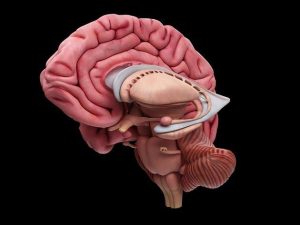

Hasta hoy día, se tenía el conocimiento de que un factor clave para superar algunas adicciones/trastornos mentales, se encuentra en la vía de recompensa más antigua y conocida: el sistema dopaminérgico mesolímbico, compuesto por neuronas que se proyectan desde el área tegmental ventral hasta el núcleo accumbens, una estructura clave en la mediación del procesamiento emocional y de la motivación.

Los investigadores descubrieron que aproximadamente el 30% de las células del área tegmental ventral -que es parte del cerebro medio- son neuronas GABA.

Mediante ejemplares de ratones machos y hembras, los científicos demostraron que las neuronas GABA de largo alcance que van desde el área tegmental ventral hasta el núcleo accumben ventral, pero no dorsal, participan en el comportamiento de recompensa y refuerzo.

Es una memoria que se encuentra en las partes emocionales del cerebro humano (sistema amigdalino); diferente al de las partes corticales, y motivan tus acciones (el “craving”, el deseo o el ansia que se activa cuando se consume drogas).

La gran motivación que genera la droga – que te hace un esclavo de ella- normalmente activa a su vez procesos para compensar, como la capacidad cognitiva, y que te ayuda a decir: “Esto se me antoja muchísimo, pero no debo hacerlo”.